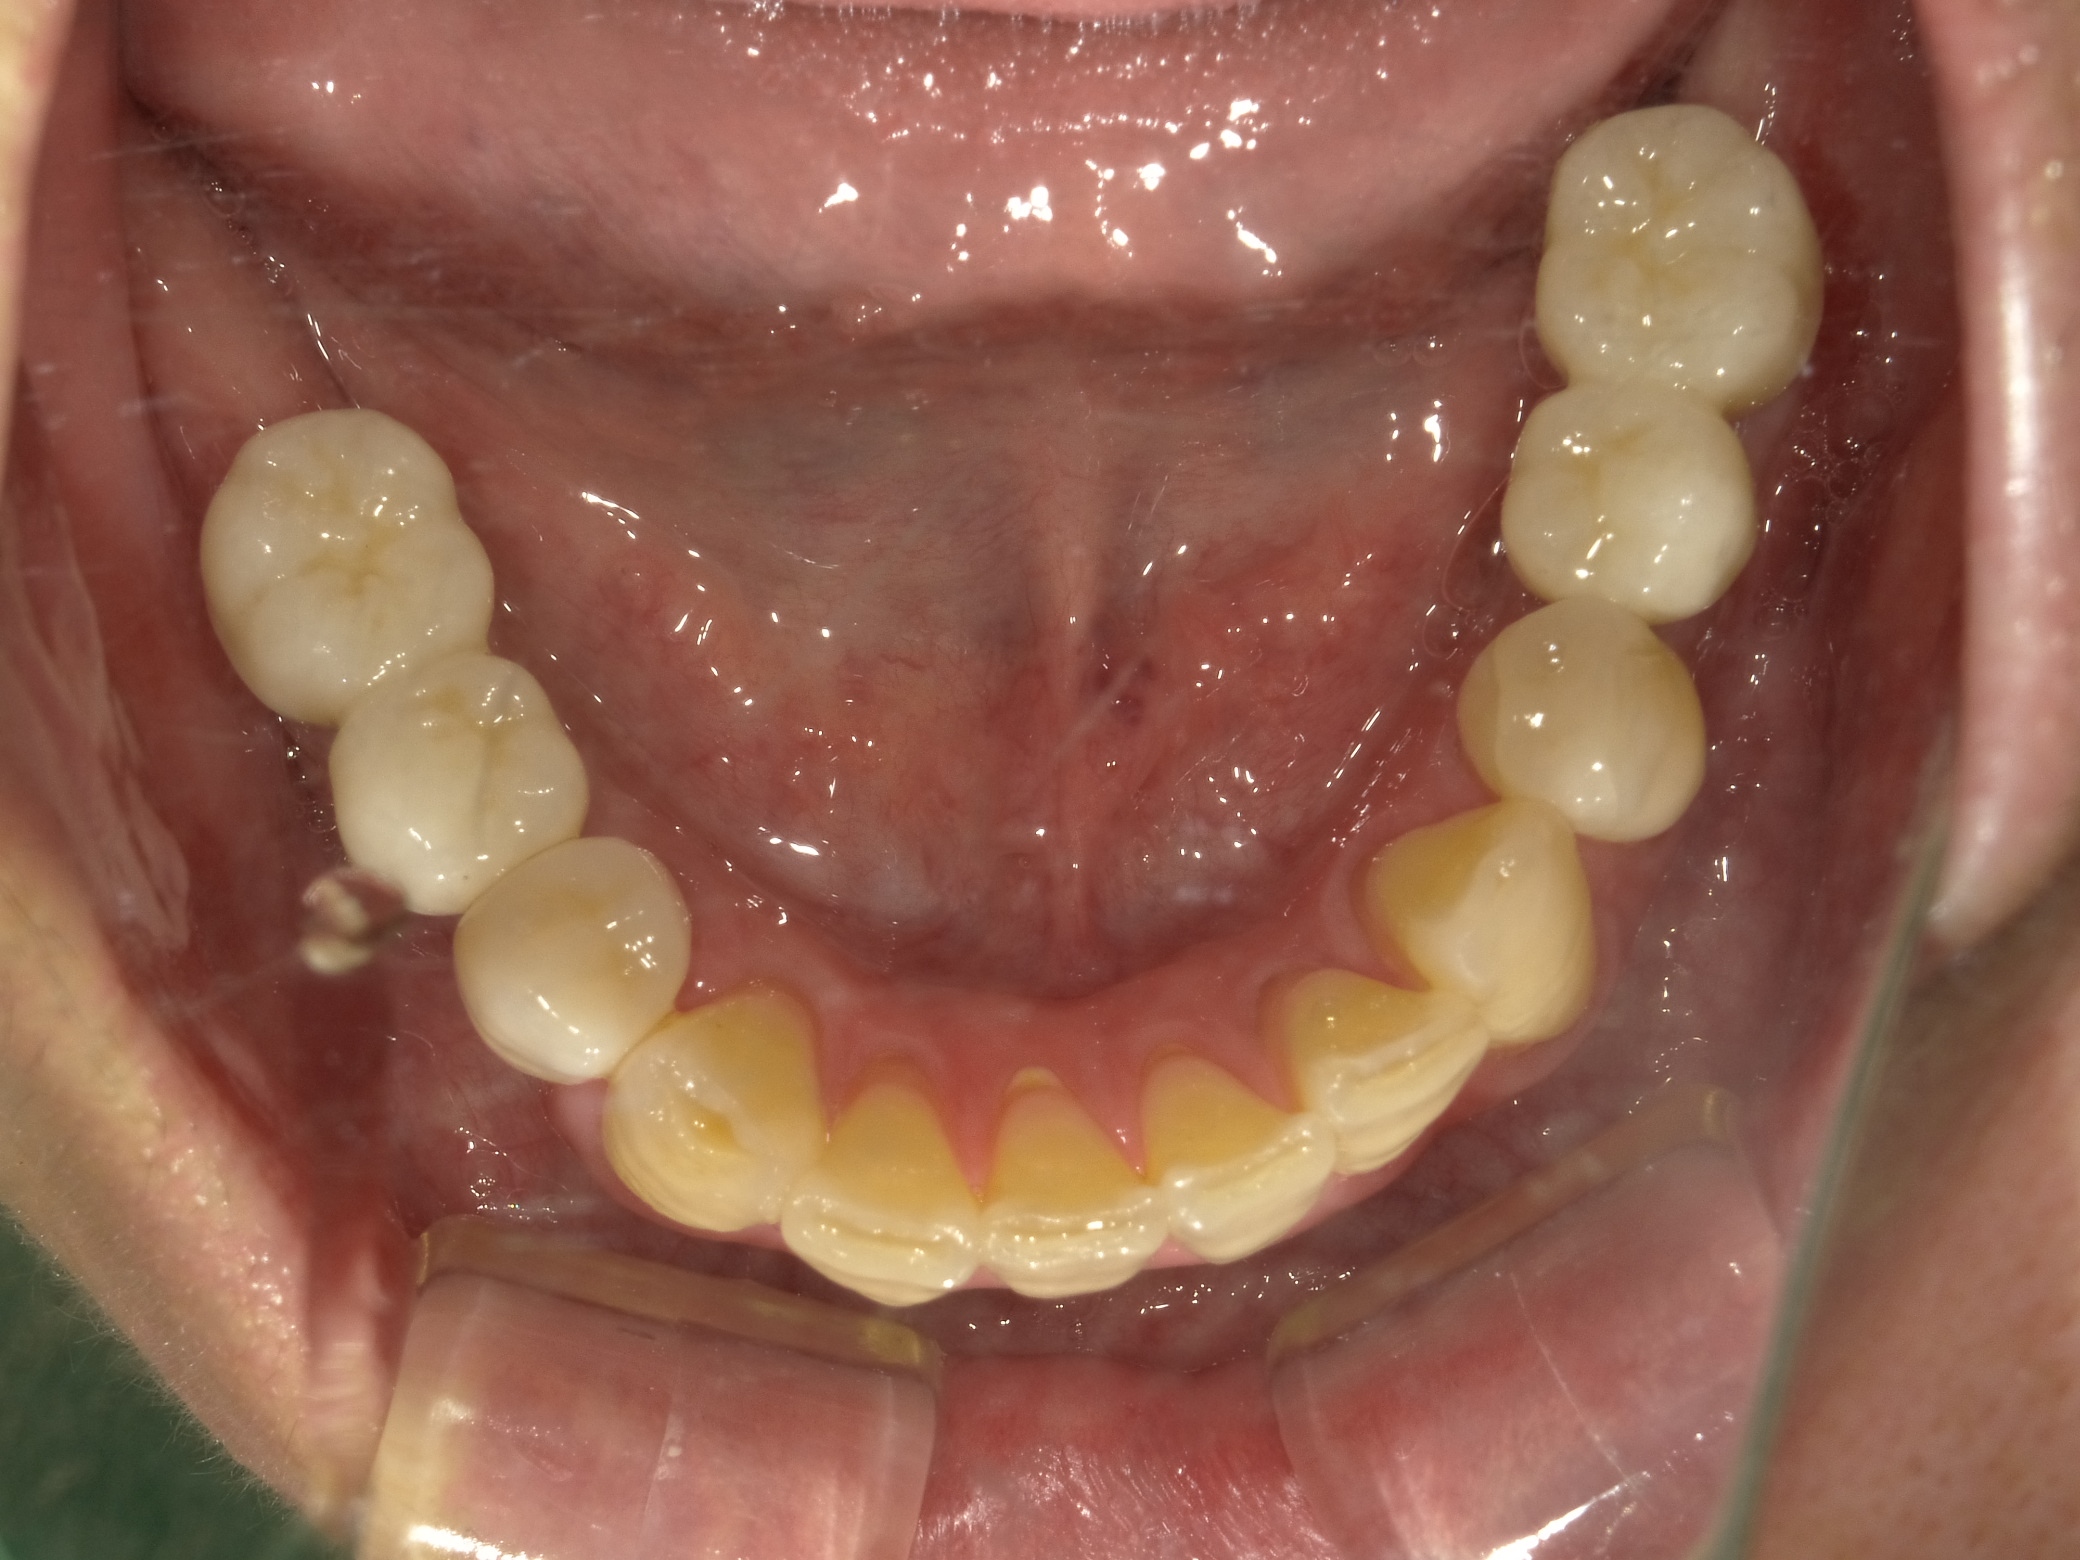

BEFORE

主訴

全体的に見た目を綺麗にしたい。奥歯でしっかり噛みたい。

診断名・主な症状

臼歯部欠損

年齢

65歳

治療内容

インプラント埋入(左下5・6,右下5・6,左上4・6)

サイナスリフト(左上4・6)

ジルコニアBr(右上6−左上3)

E –MAX CAD(右下4)

セラミックインレー(左下4)

治療期間/

通院回数

約1.5年/約20回

費用

インプラント治療 約2,000,000円

その他被せ物治療など 約1,000,000円

合計 約3,000,000円

*いずれも税込

インプラント治療の

リスク・副作用

定期的なメインテナンスを行わない場合、インプラントが脱落する可能性があります。被せ物は経年的な劣化で欠ける可能性があります。